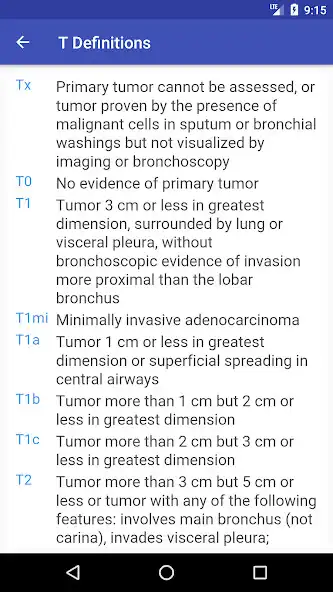

Lung cancer is the most common malignancy in the United States. The prognosis of lung cancer depends on its stage. This application calculates the stage of the tumor according to the TNM classification, where T represents the characteristics of the primary tumor, N describes the presence or absence of spread to certain lymph nodes, and M details whether the tumor has spread to other structures in the body.